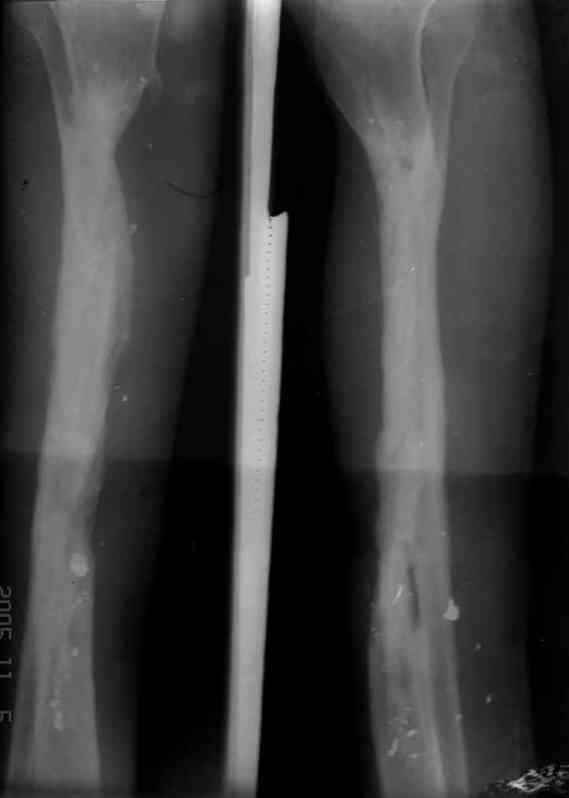

5, 6 - через 2,5 мес после травмы выполнен закрытый остеосинтез блокируемым штифтом.